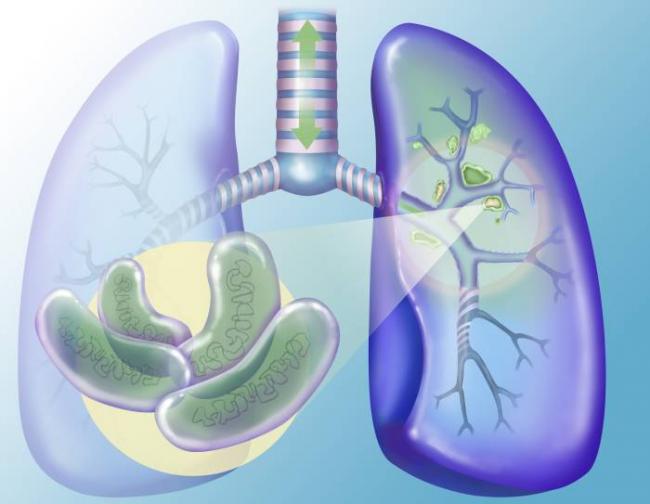

Микробактерии, попадая в организм, распространяются бронхолегочным, гематогенным и лимфогенным путем. В легких начинается образование отдельных или множественных бугорков. При закрытой форме туберкулеза микробактерии размещаются внутри этих бугорков и находятся в изолированном состоянии, не выделяя инфекции в окружающую среду. В этом случае окружающие не могут заразиться.

При открытой формы туберкулеза происходит выделение возбудителей, попадающих в мокроту и передающихся в дальнейшем воздушно-капельным путем. Такие больные представляют серьезную опасность для здоровых людей, а риск заражения возрастает.

Что такое открытая форма заболевания и чем она отличается от закрытой? Анализы такого человека на палочку Коха будут в любом случае положительны, но при закрытой форме очаги патогенов локализуются, например, в лёгких, и никак себя не проявляют. Они не выходят за пределы этих бугорков, скоплений. Человек считается неопасным. Но любое столкновение с раздражителями и провоцирующими факторами – и закрытая форма быстро перейдёт в открытую. В этом случае очаги начинают раскрываться, и палочки Коха вылезают наружу. Они вызывают активный воспалительный процесс. Распространяясь с кровотоком по всему организму, любые биологические жидкости такого человека становятся потенциально опасными.